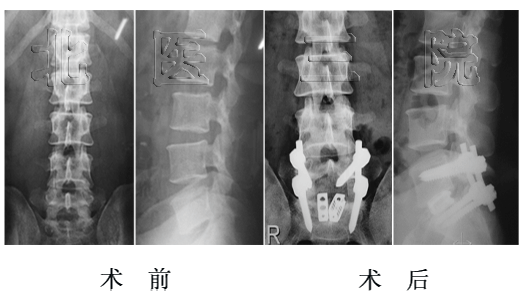

女性,65岁,成人腰椎侧凸,侧凸角度46o,行侧凸矫形固定、植骨融合,术后侧凸角度减小为5o

女性,14岁, L5重度发育不良性滑脱(ⅴ°),行前后联合入路L5椎切除、S1上终板截骨、L4-S1固定融合术。